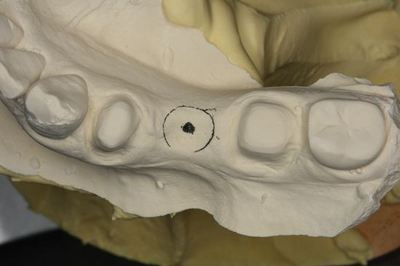

模型上で埋入ポジションのシミュレーションをします。

CTデータと重ね合わせて3次元的角度を決めます。

即時重合レジンでドリルガイド(サージカルステント)を作製します。